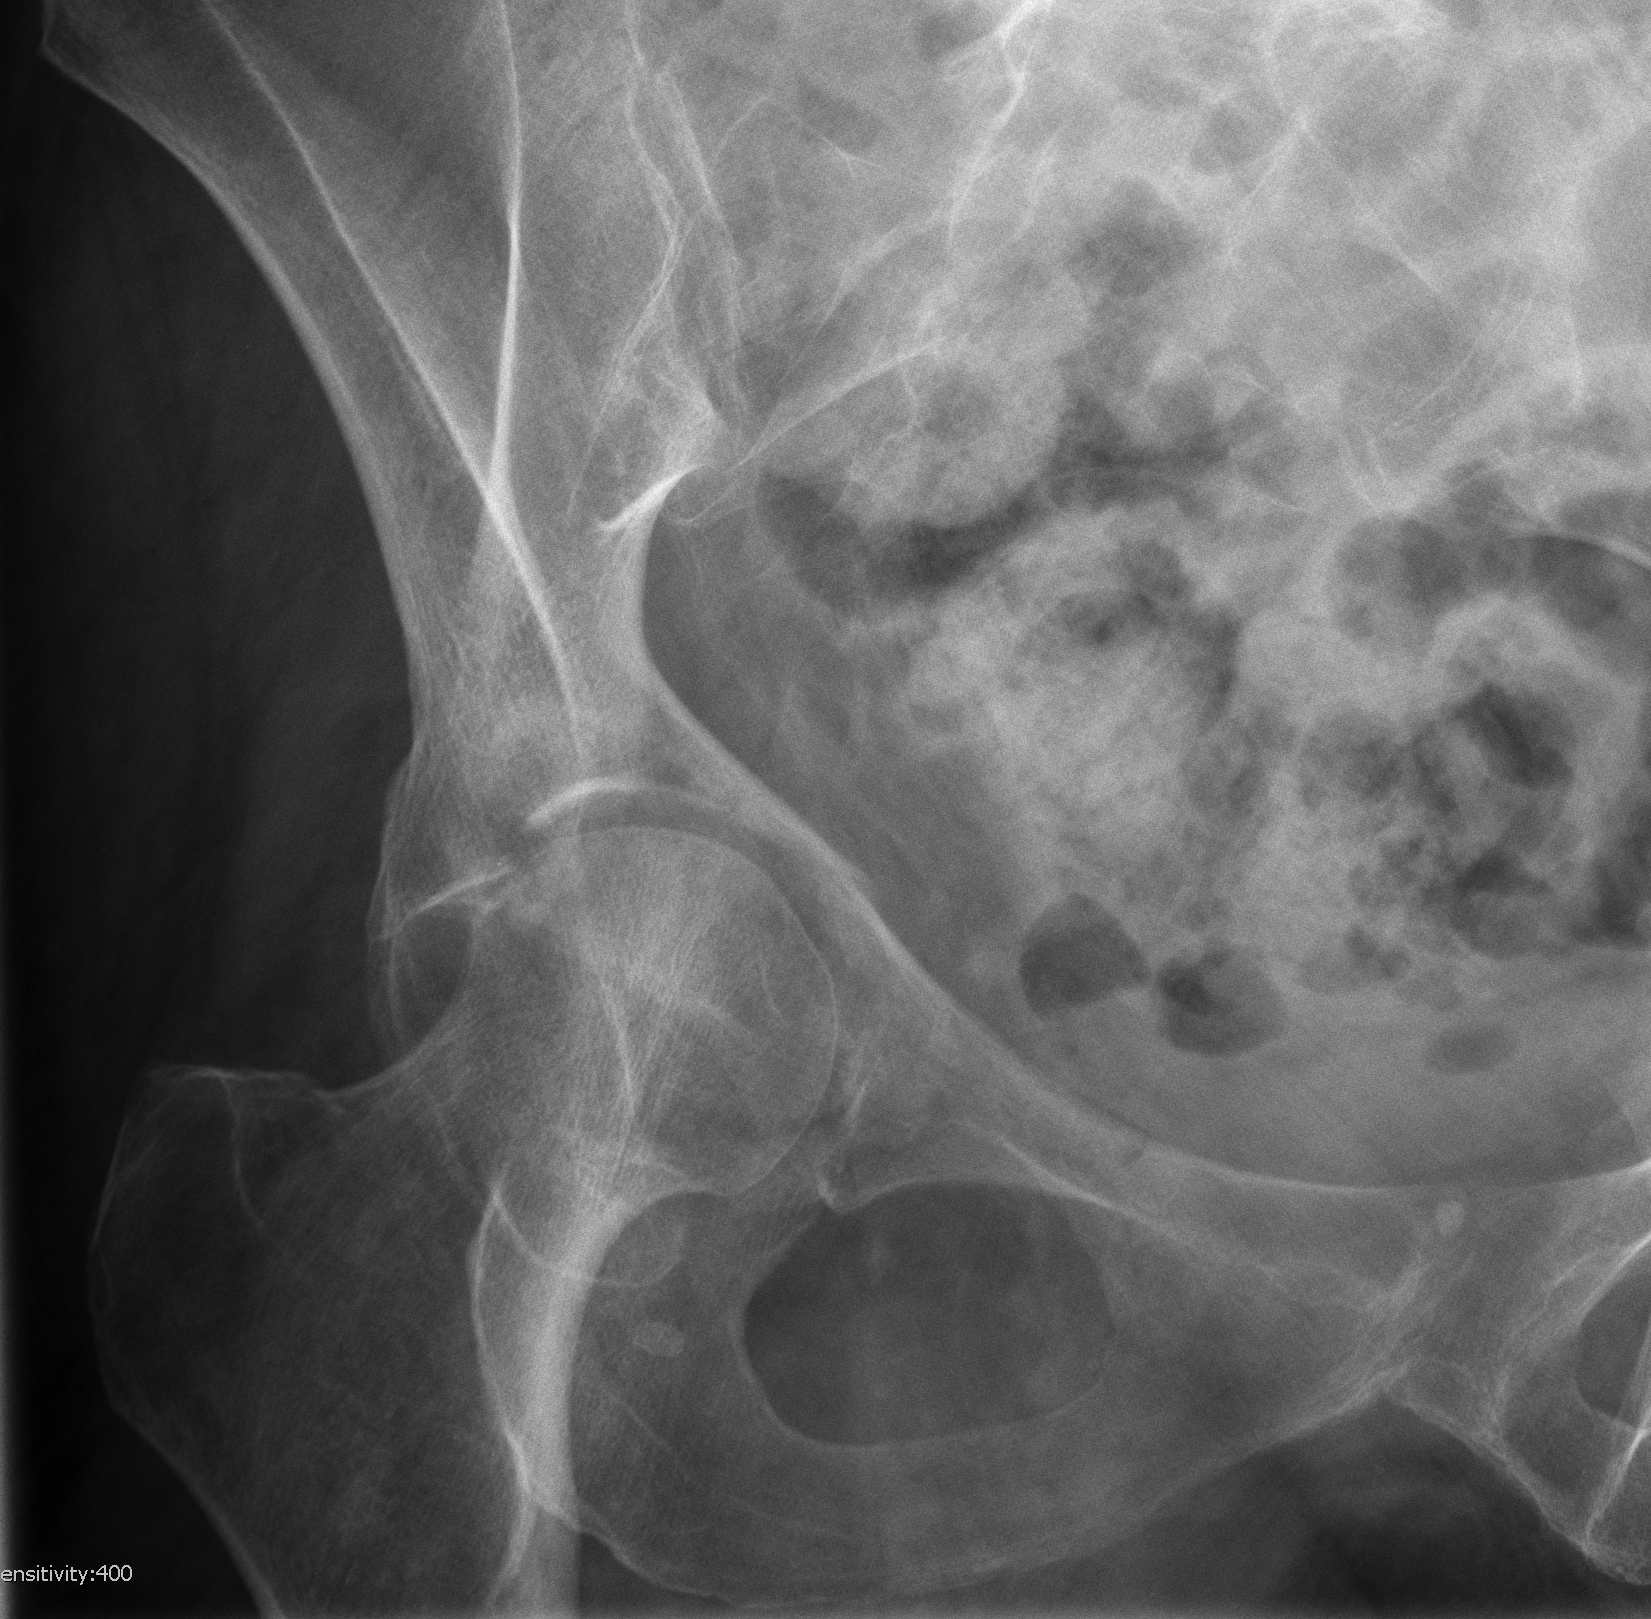

X-ray / 5 standard views

AP / Six X-ray Landmarks

1. Iliopectineal line

- along pelvic brim to pubic symphysis

- anterior column

2. Ilioischial Line

- pelvic brim to ischial tuberosity

- posterior column

- formed by posterior 4/5 of quadrilateral surface ilium

3. The Teardrop

- lateral: subchondral bone condensation at anterior margin of cotyloid fossa

- medial: anterior flat part of quadrilateral surface of iliac bone

4. Roof of acetabulum

5. Anterior rim of acetabulum

- semilunar

6. Post rim of acetabulum

Judet views / 45o obliques

Internal Oblique / Obturator Oblique

- affected side rotated forward

- anterior column + posterior wall

External Oblique / Iliac Oblique

- unaffected side rotated forward

- posterior column + anterior wall